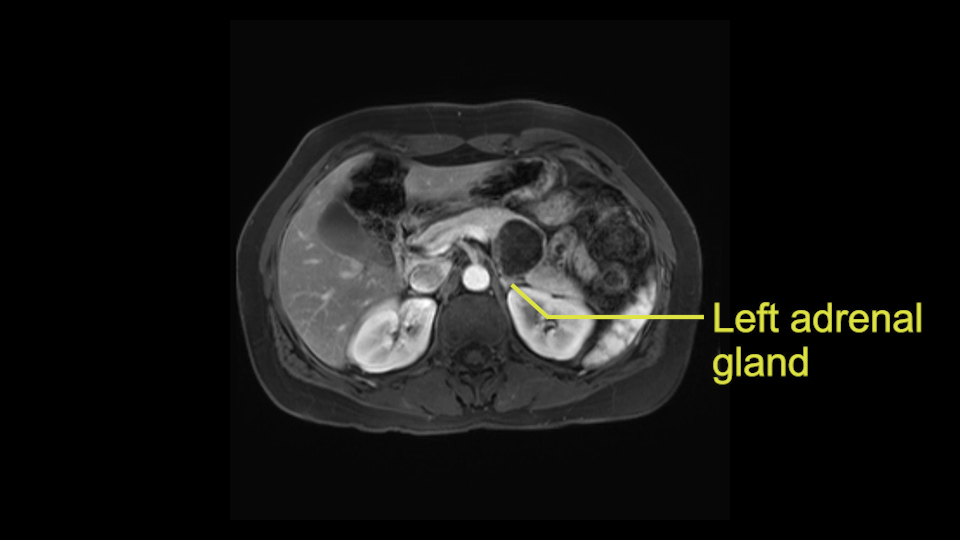

The lesion also is quite posterior. While the plane between the cyst and the left adrenal gland is often preserved, we do have to pay attention here so that we remain in the right plane and maintain our margin here. Occasionally in these cases, en bloc adrenalectomy needs to be performed.

Sometimes with even benign lesions of the spleen you can have quite a lot of inflammation in the retroperitoneum and so I do think about and wonder whether I will have some difficulty in the retroperitoneum and I usually look at the scan for that purpose. It looks like there is no inflammation in the retroperitoneum. It does look very close to the patient’s left adrenal gland but knowing the planes and suspecting that there isn’t any active inflammation, this should be able to come off the left adrenal gland without any difficulty. But obviously prepared to take some of the left adrenal if that’s necessary in this procedure. So those are my procedure-specific slowing down moments in a distal pancreatectomy when I’m considering a laparoscopic approach. I think the patient-specific slowing down moments in this particular case I have discussed with the procedure-specific moments. I don’t really see any other issue or that I have to be careful of or consider.

So first, I'll show you the scan. Here's the traditional view, where you see the cyst, which is in the body of the pancreas. And you see over here, it's got a quite thick wall. And going a little bit back also, here you see a septation which is very important, because I think a septation is what separates this from, for instance, the pseudocyst of the pancreatitis. And also the location of the cyst you see here, abutting the adrenal gland and going down a bit more, it's also quite close to a bowel loop. So when thinking about this cyst: female, the location in the body of the pancreas, thick wall, septation, and as you can read in history, it was basically asymptomatic, so no signs of pancreatitis. So, this probably all points towards a mucinous cystic neoplasm.